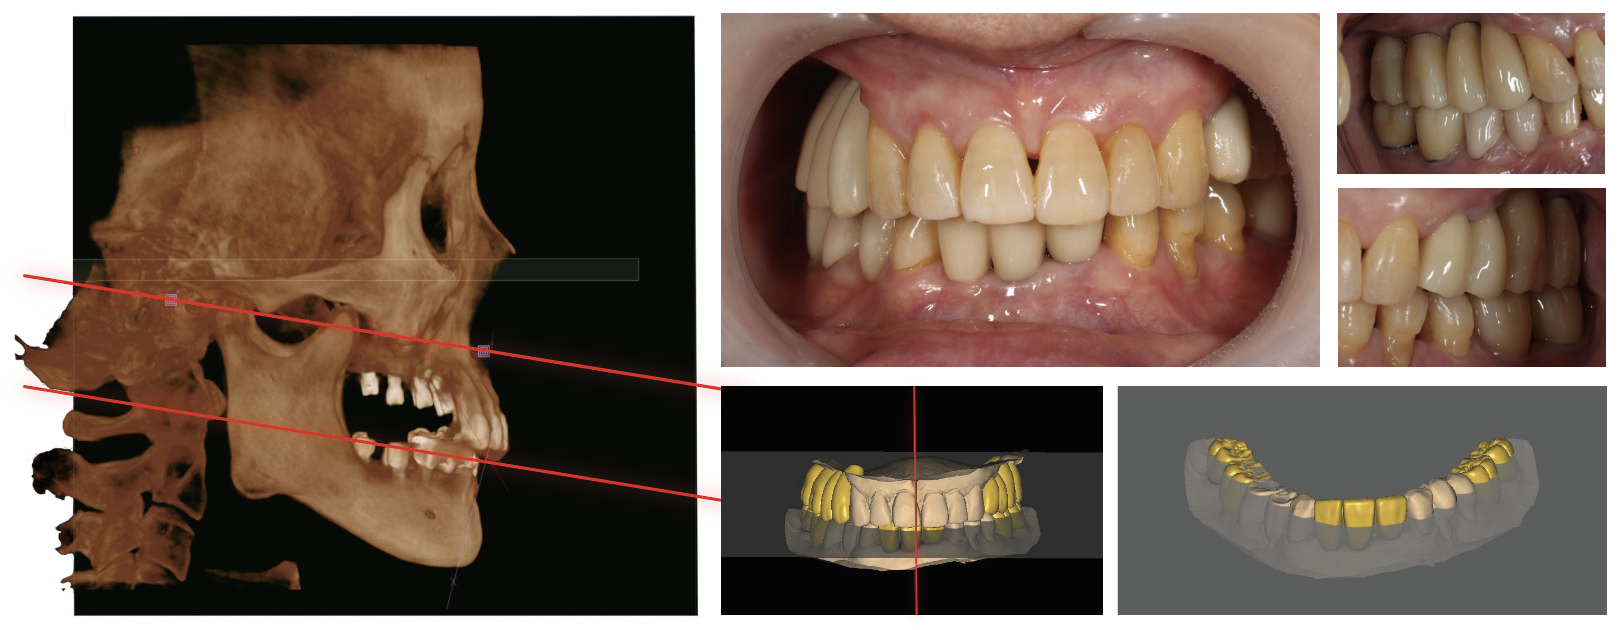

AI的增強在CBCT應用

Dentium-AI自動檢測掃描圖像上的位點進行正畸分析。

AI咬合平面:有助于發現無牙頜患者的咬合面,作為參考。rainbow 3Dviewer附帶此功能,無需額外付費。